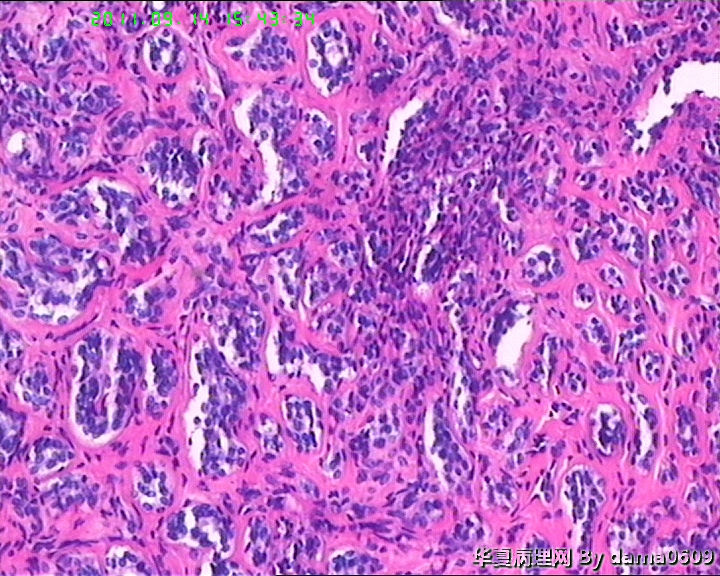

女,22岁,乳腺肿物,病史不详。

不整形软组织肿物一个,V:2.0x1.5x1.5cm。无包膜。切面实性,灰白色,小结节状,质中。

镜下结构复杂,图3、4、8、10、11、12、13、15、17、18、19、20为肿物中央区域,占标本大部分,图1、2、7、14为肿物边缘部分,图5、6、9、16、21为二者交界处。有点乱,不好意思,请老师别介意。

请教老师,诊断:硬化性腺病,可以吗??谢谢!!

• 乳腺肿物,急于求教!!图1

图1

会诊结果::(乳腺)腺管腺病,伴纤维腺瘤形成。

该例患者经上级医院会诊,回报:(乳腺)腺管腺病,伴纤维腺瘤形成。